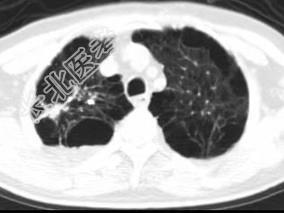

- 单项选择题男,76岁, 气喘数年,胸痛一月余, 结合影像图像,选择最可能的诊断 ( )

A、右上肺结核球

B、肺间质纤维化

C、右上肺瘢痕癌

D、右上肺错构瘤

E、右上肺肉瘤